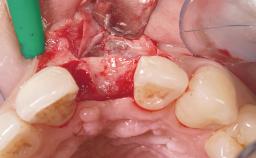

Immediate Placement of an Implant in a Maxillary Right Central Incisor Site

A 30-year-old female patient was referred to the office for the treatment of tooth 11. Her chief concern at the initial visit was to inquire, “Why is my tooth pink?” Upon clinical examination, it was determined that tooth 11 had a previous history of trauma and that the clinical crown had become noticeably pink in color as a result of internal resorption. This diagnosis was confirmed radiographically, indicating a large radiolucency involving the central and distal portions of the clinical crown. It was determined that restoration of this tooth was not possible, and that extraction was indicated. The presence of a mid-line diastema, which the patient wanted to reproduce, directed the treatment plan for tooth replacement utilizing a dental implant.

Soft Tissue Grafting None

Soft Tissue Anatomy Intact Defective

Bone Volume Horizontally and vertically sufficient Horizontally deficient Deficient vertically or deficient vertically AND horizontally